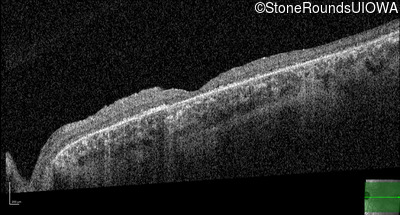

Optical Coherence Tomography - Right - 20/100 -1 sc

Exemplar / OCT Stack

OCT Stack